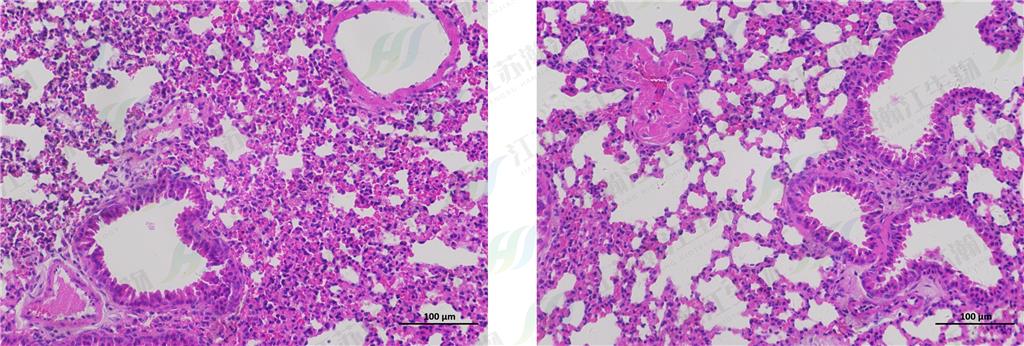

2.肺脏、支气管组织HE染色